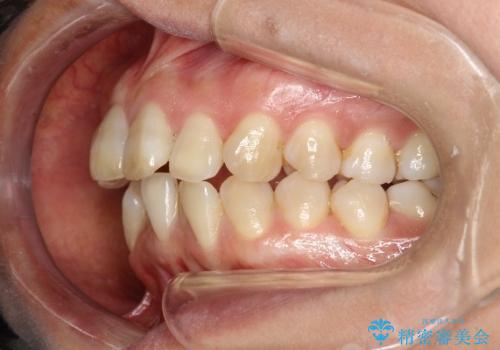

- 上下の歯並びにガタつきがあり、また、上下前歯の前後のズレが大きく上の前歯が突出しています。

インビザラインではガタつき(叢生)の改善だけでなく、上下の前後的なズレについてもアプローチが可能です。

インビザラインの特色を生かした歯牙移動計画を作成し、非抜歯にて治療を行いました。